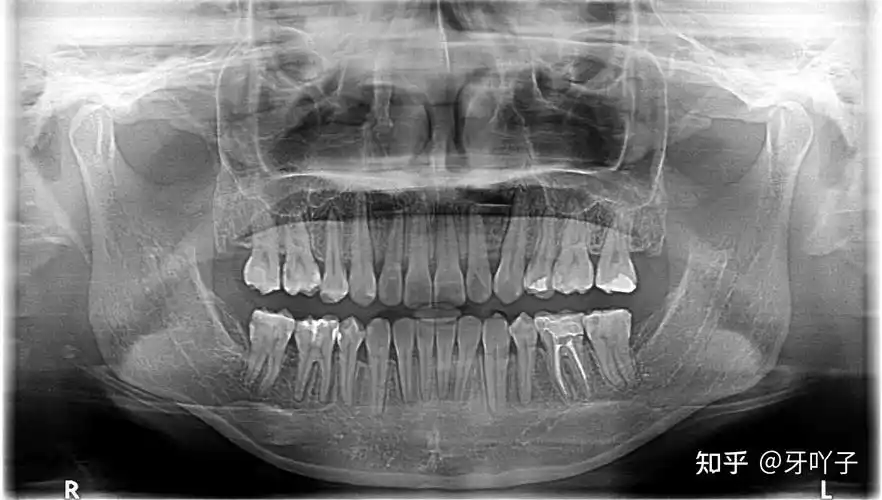

我的牙齿拍片 上左4 上右4 下左4 下右5 全副牙32颗,我有28颗.